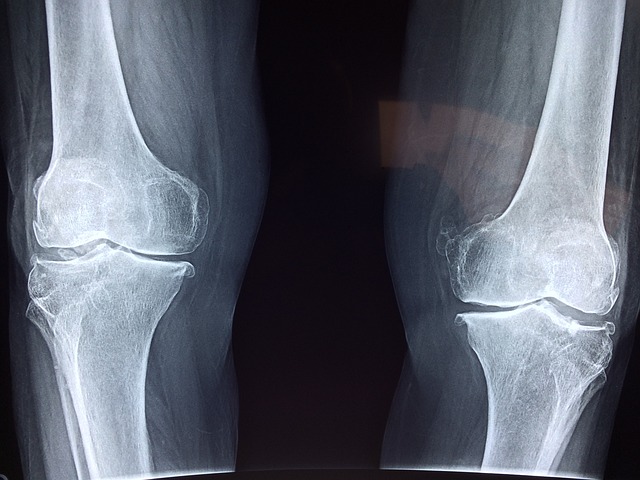

류마티스 관절염의 초기 증상

류마티스 관절염의 초기 증상은 일반적인 관절 통증과 비슷해 많은 사람들이 쉽게 지나칠 수 있습니다.

하지만 증상이 나타난다면 류마티스 관절염을 의심해보고 진료를 받는 것이 좋습니다.

- 양쪽 손목, 양쪽 무릎과 같은 대칭적인 관절에서 통증이 발생합니다.

- 관절의 붓기와 열감

- 통증이 있는 관절 부위가 붓고 만졌을 때 열감이 느껴질 수 있습니다.